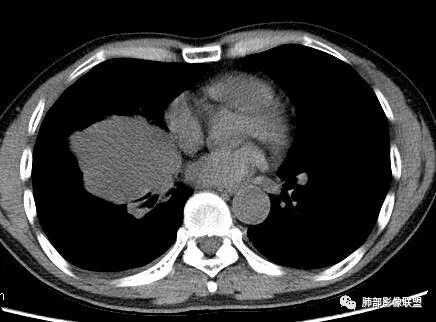

3.肿块常常较大,甚至巨大,病灶边界一般清楚,影像上常有假包膜样结构、有膨胀性生长的特点,影像科医师有时甚至会纠结其来源于肺部或是胸壁纵隔。常见的肺癌肿块,很少有机会能长成这样的规模。

5.病灶密度大多不均,不规则坏死液化,少数病例出现钙化。增强扫描常观察到由外而内的厚壁不均匀强化,中央半岛样强化等等,厚壁中或实性区常能显示血管影。一些病灶中央呈现边界清楚囊样变。

6.病灶侵犯胸膜时可以出现胸水,病灶可以侵犯胸壁并引起相应临床症状。